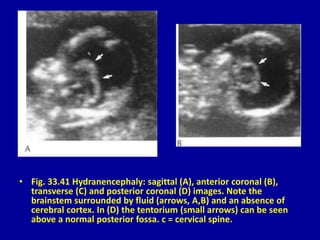

• Fig. 33.41 Hydranencephaly: sagittal (A), anterior coronal (B),

transverse (C) and posterior coronal (D) images. Note the

brainstem surrounded by fluid (arrows, A,B) and an absence of

cerebral cortex. In (D) the tentorium (small arrows) can be seen

above a normal posterior fossa. c = cervical spine.

• Fig. 33.41Hydranencephaly: sagittal (A), anterior coronal (B), transverse (C) and posterior coronal (D) images. Note the brainstem surrounded by fluid (arrows, A,B) and an absence of cerebral cortex. In (D) the tentorium (small arrows) can be seen above a normal posterior fossa. c = cervical spine.